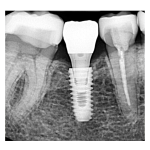

治療途中のインプラント症例

治療途中のインプラント症例です。 主訴 抜歯した部分を噛める様にしたい  ...